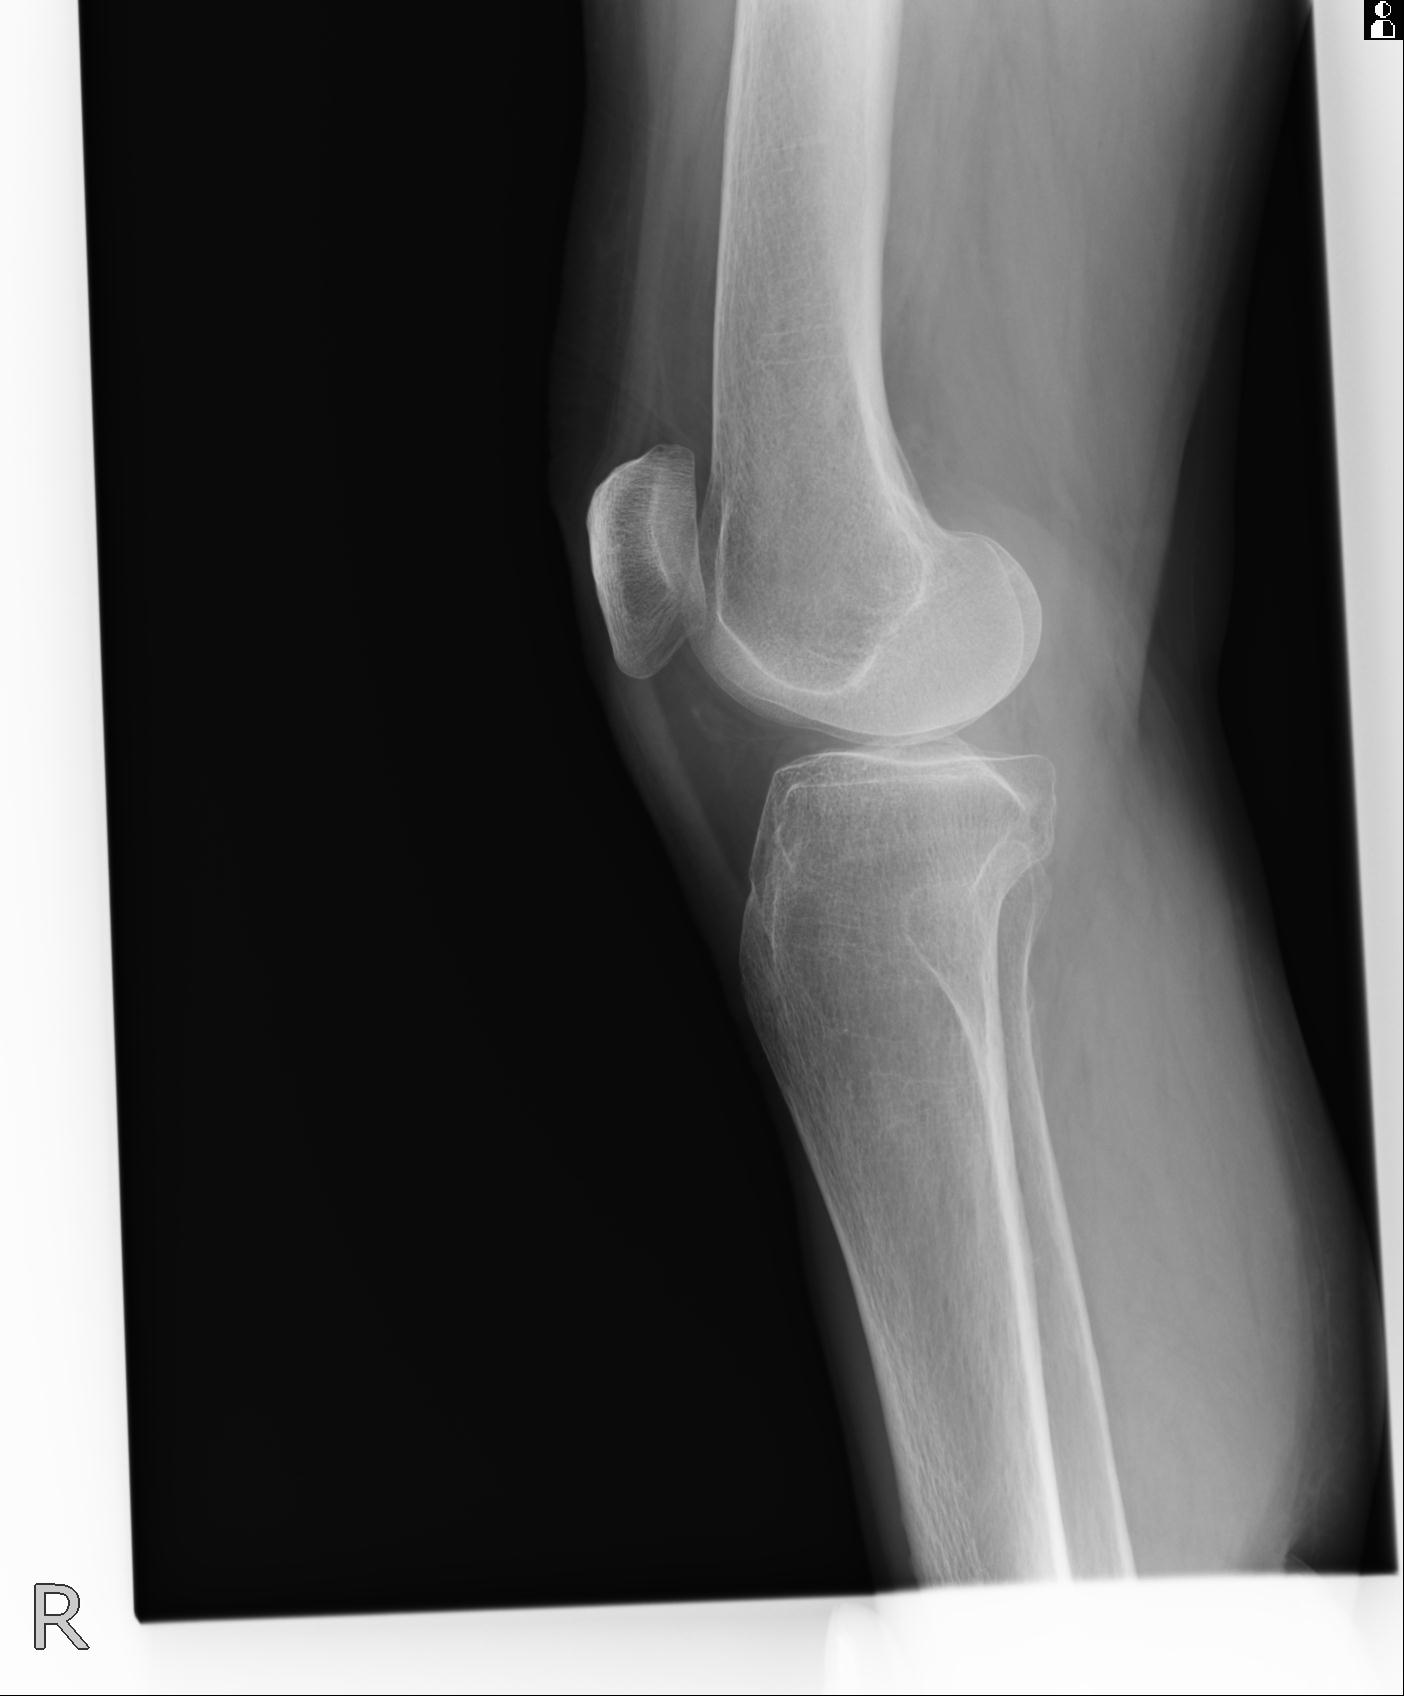

49554 3/13 膝 4R 3/16 4R 1/18 2R 78歳男性 膝蓋骨骨折